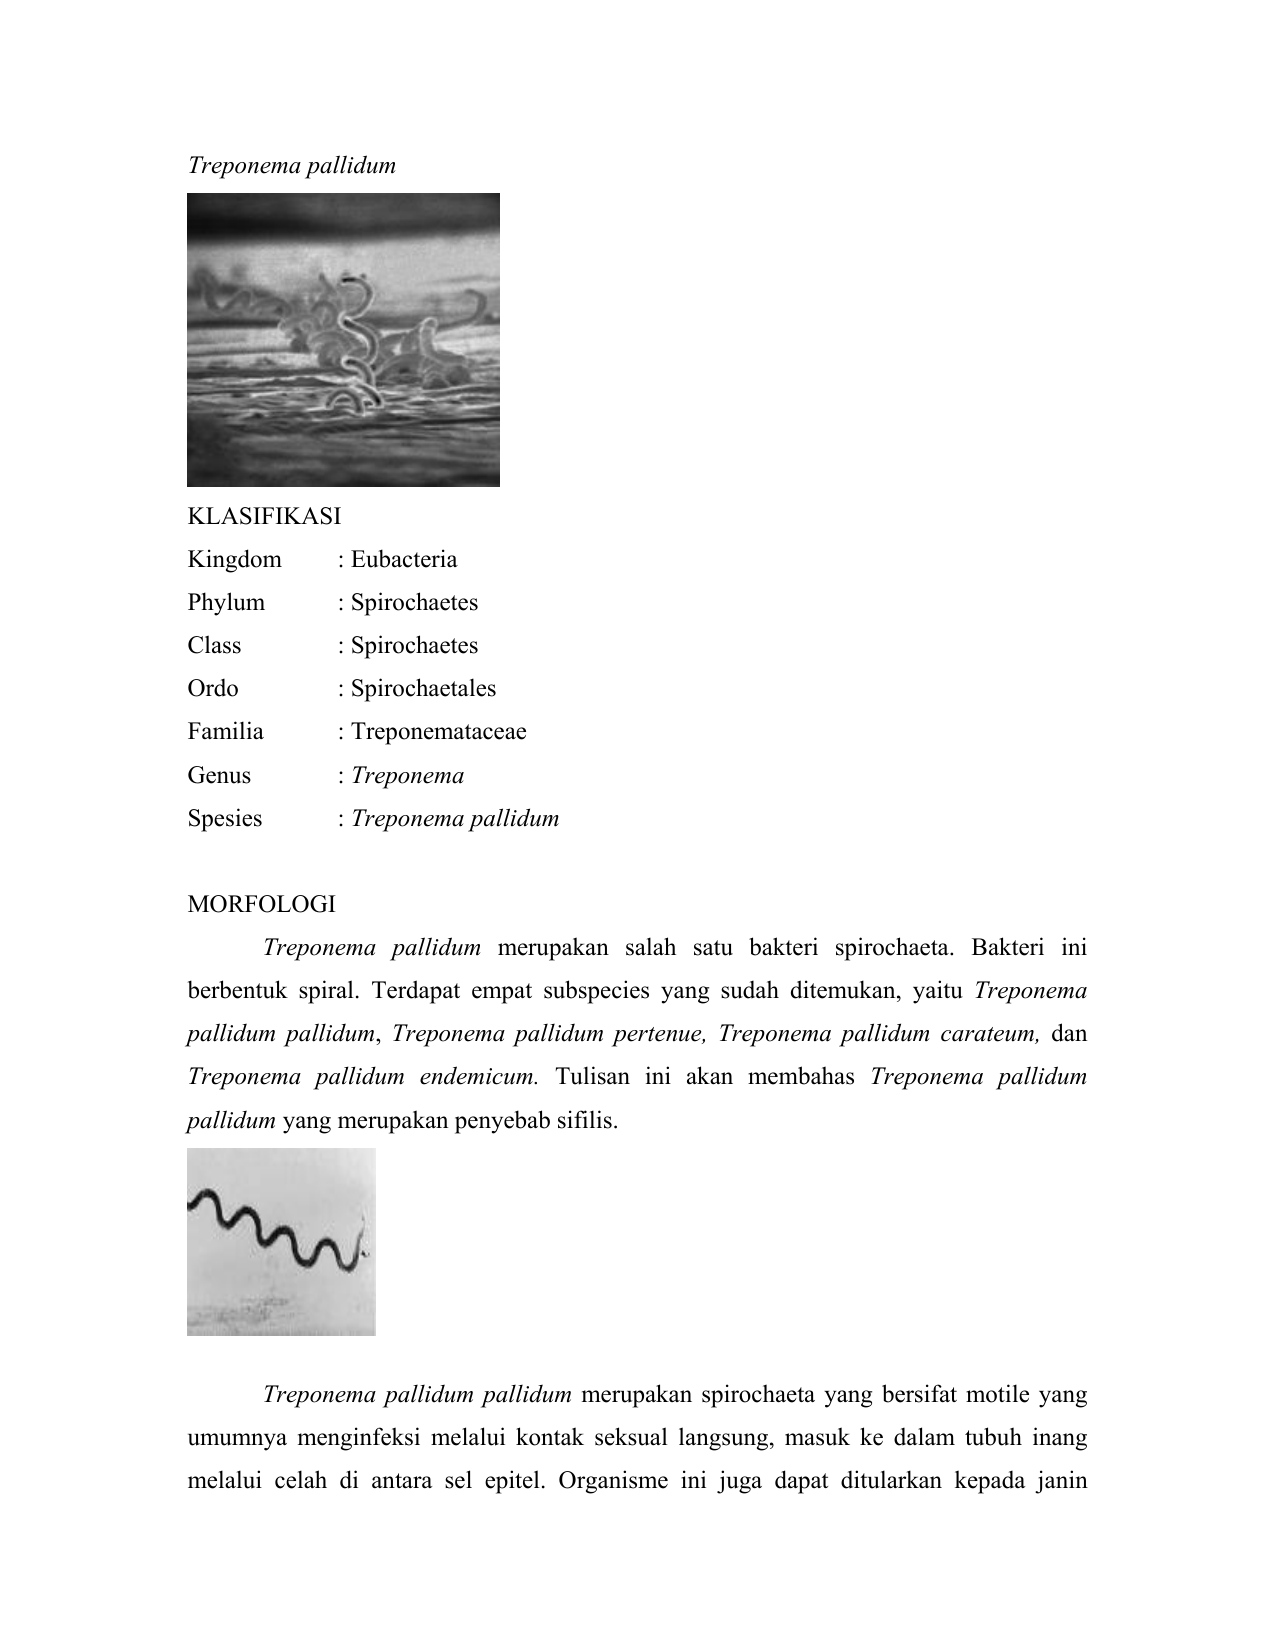

Treponema pallidum merupakan salah satu bakteri anggota filum Spirochaetae. Bakteri ini berbentuk spiral. Terdapat empat subspesies yang sudah ditemukan, yaitu …

Treponema pallidum merupakan salah satu bakteri anggota filum Spirochaetae. Bakteri ini berbentuk spiral. Terdapat empat subspesies yang sudah ditemukan, yaitu …